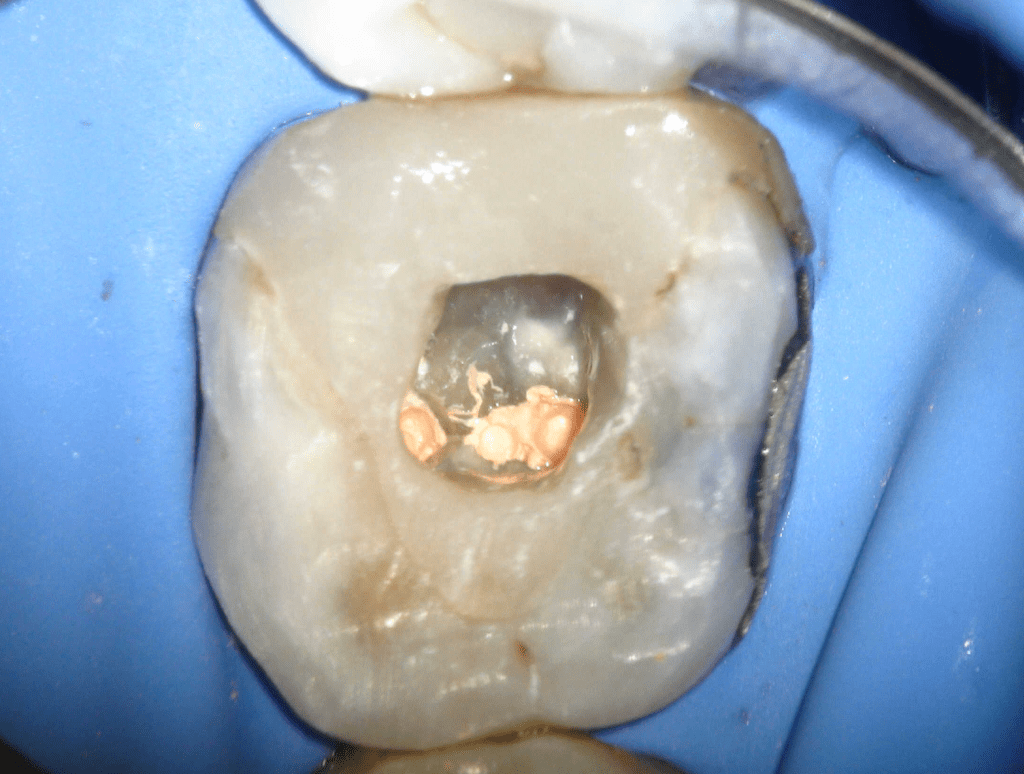

Fisura, remoción amalgama para explorar